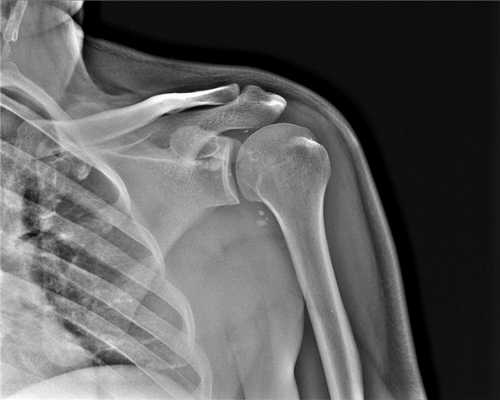

2. Рентгенография при остеоартрозе плечевого и локтевого суставов:

• Плечевой сустав:

о Нормальная плотность костной ткани

о Субхондральный склероз

о Формирование остеофитов:

- Вокруг суставной впадины лопатки; чаще всего наилучшим образом визуализируются в аксиллярной проекции

- Вокруг анатомической шейки плечевой кости (краевые):

Наибольшее разрастание направлено вниз и кнутри в подмышечный карман

о Субхондральные кисты

о Сужение суставного пространства

о Подвывих в плечевом суставе может формироваться на фоне патологических изменений:

- Верхний подвывих головки плечевой кости на фоне хронического повреждения вращательной манжеты

- Задний подвывих головки при хронической нестабильности (визуализируется при рентгенографии в аксиллярной проекции)

о Внутрисуставные свободные тела:

- Визуализация затруднена, если сустав не растянут выпотом

- Ищите оссифицированные тела в подмышечном и подклювовидном заворотах

о Рентгенография позволяет установить диагноз при ОА от легкого до умеренного

Когда КТ плечевого сустава лучше, чем МРТ плеча

Компьютерное рентгеновское исследование плеча больше рекомендовано при проведении диагностики костной составляющей человеческого организма, а именно: травматических повреждений костей плеча человека; неправильно сросшиеся кости, наличие костных шпор; поражений костей опухолевой природы как первичных, так и вторичных; атеросклеротических изменений сосудов.